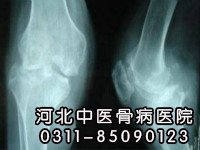

擅长中西医结合治疗各种腰椎管狭窄、膝关节骨质增生、滑膜炎、运动性损伤、骨髓炎、骨结核、股骨头坏死、等骨科疾病。